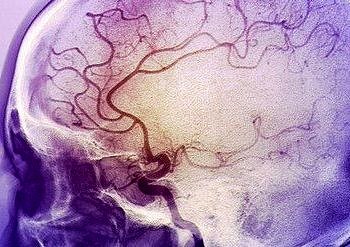

İnsanların konuşma, hareket etme, görme, duyma gibi temel fonksiyonlarını yerine getirmek için gereken enerjiyi, beyine atardamarlar taşır. İnme olarak adlandırılan...

Önlem alınmadığı takdirde kişide hayati risk ve kalıcı sakatlıklara yol açan inme, yaşam tarzında yapılacak değişiklikler ve düzenli sağlık kontrolleri...

Dünyada yılda 15 milyon kişi, Türkiye’de ise her yıl 130 bin kişi inme ya da felç geçiriyor. İnmede en büyük risk faktörleri arasında sigara kullanımı, hipertansiyon ve...

DevamıTüm dünyada bir yılda 17 milyon kişi inme geçiriyor ve 6 milyon kişi de bu hastalık nedeniyle hayatını kaybediyor. Üstelik görülme sıklığı 50 yaş ve sonrasında artsa...